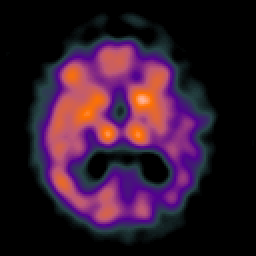

Alzheimer's disease: Perfusion SPECT -- Slice #26

[Home][Help][Clinical][Tour 1][Tour 2] Slice 26